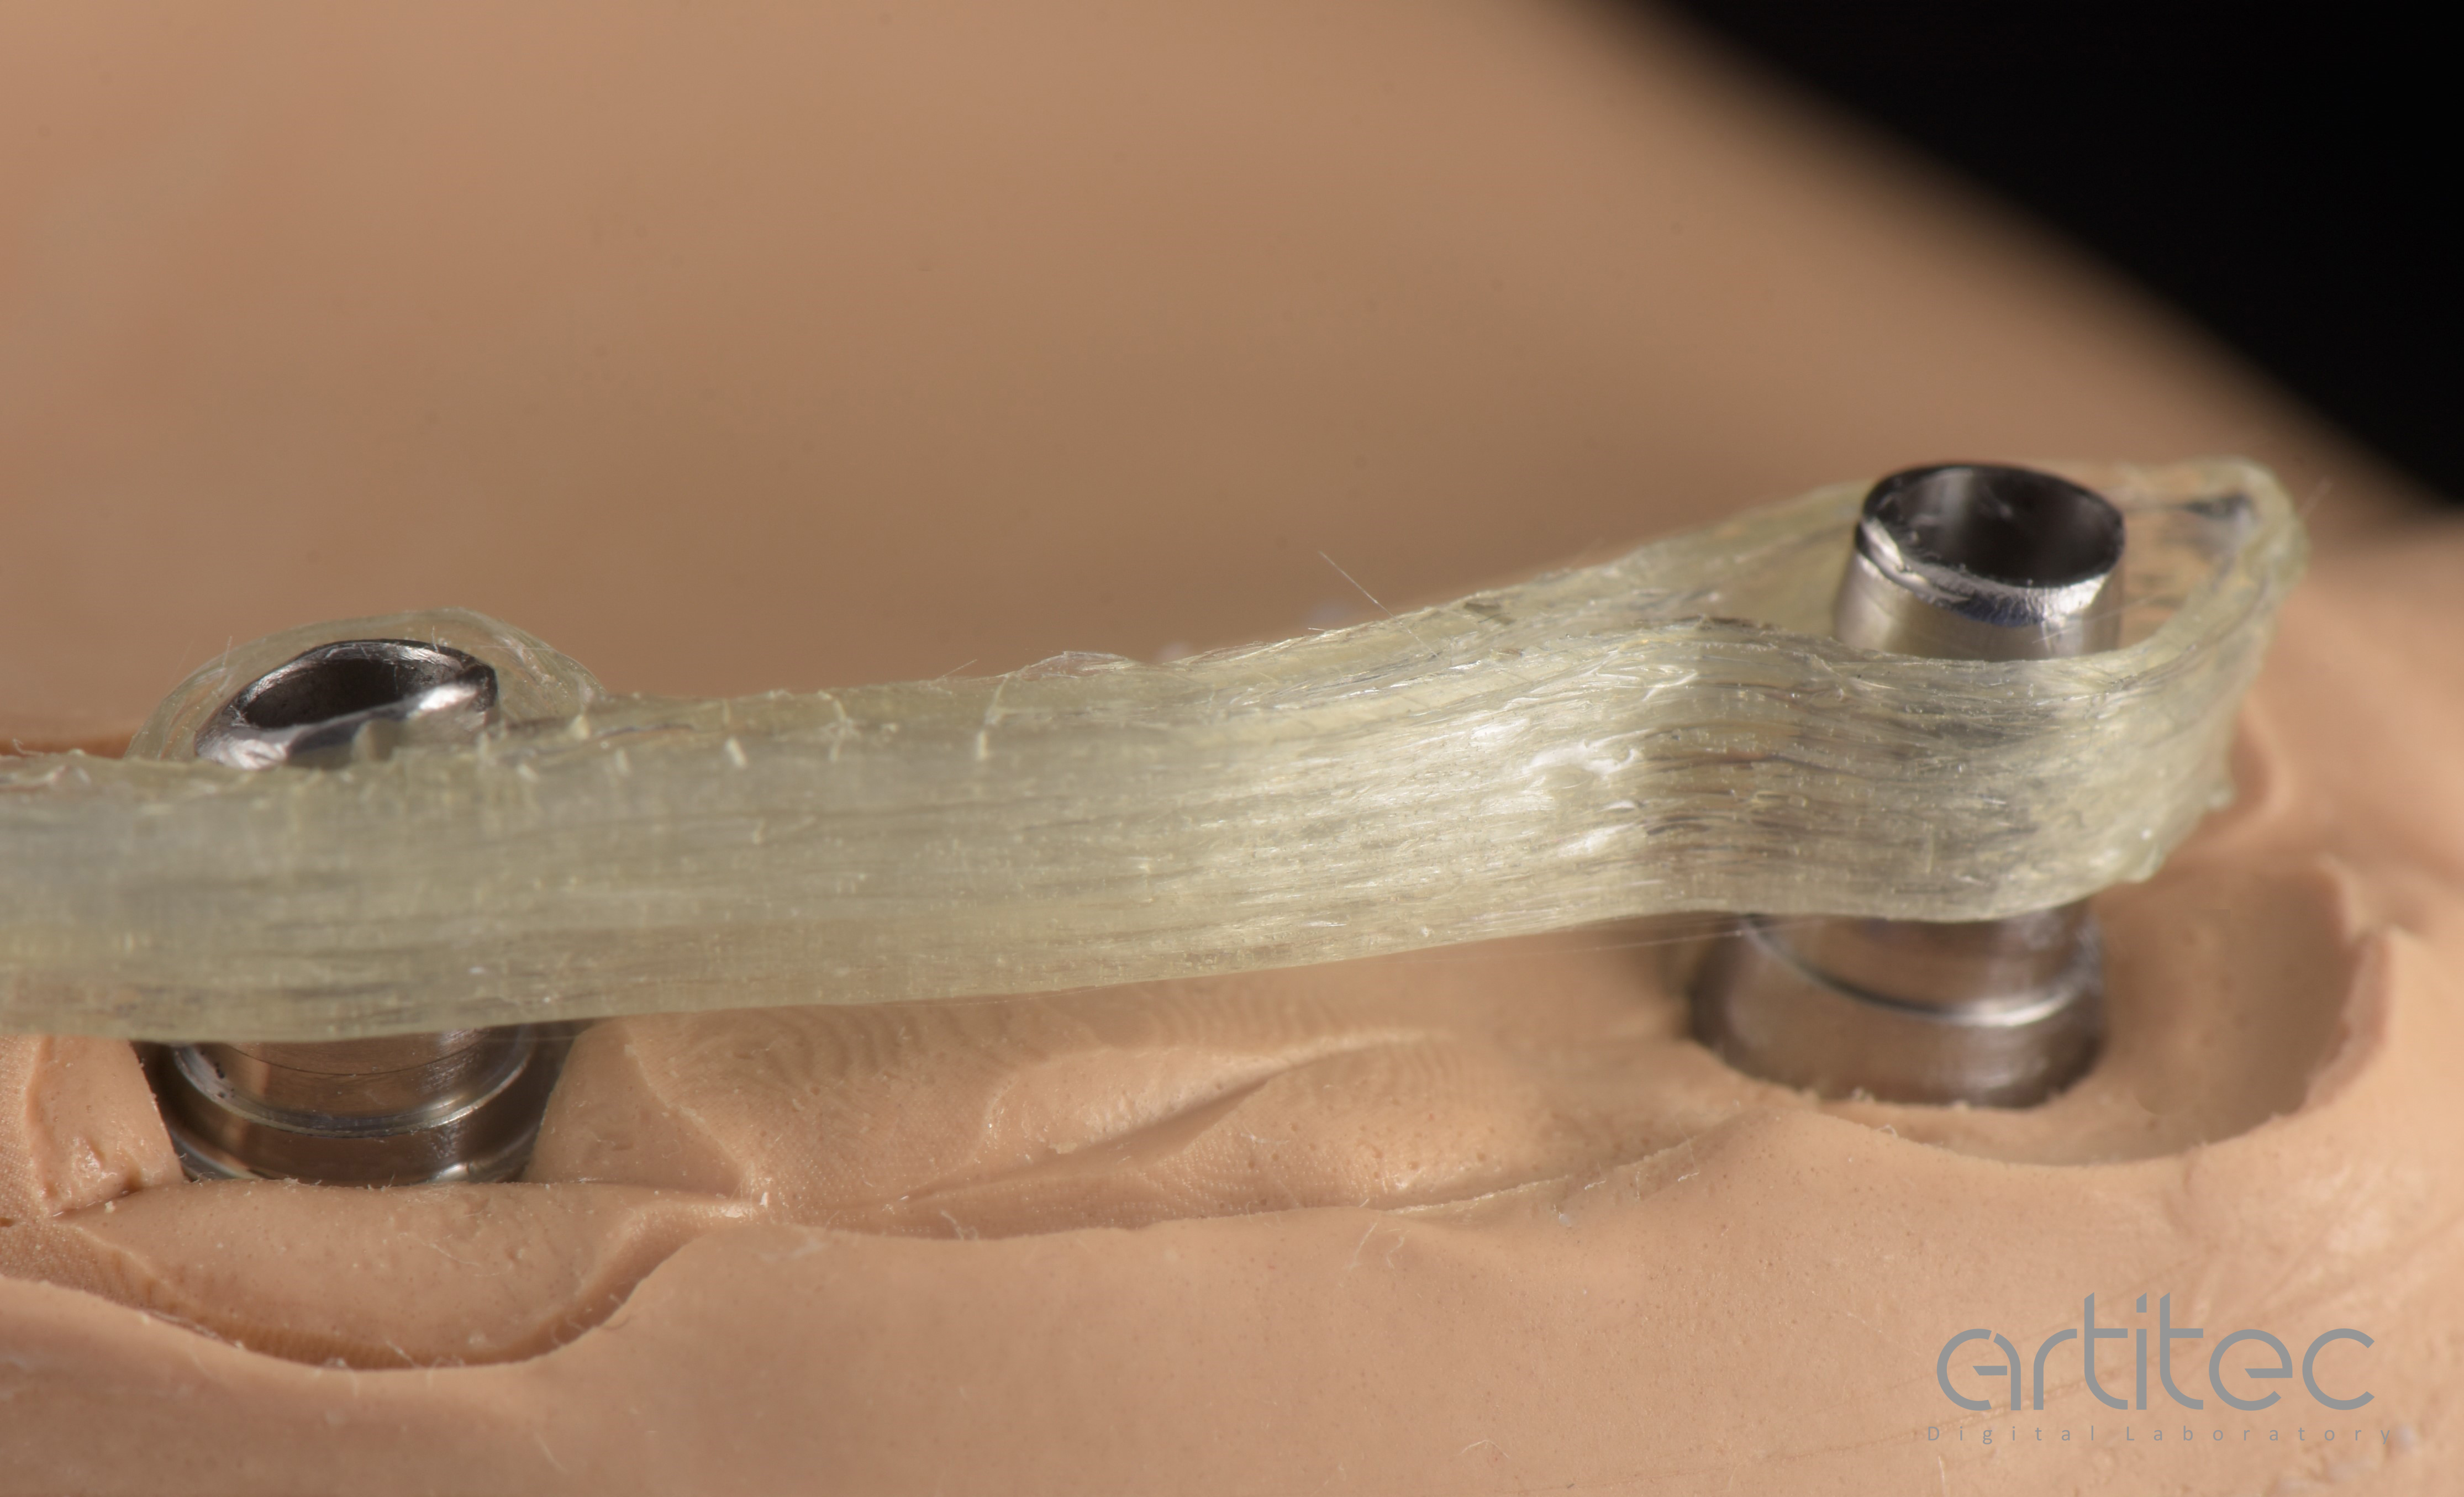

Fig. 5 Posizionamento anatomie dalle informazioni della scansione del provvisorio

Fig. 27 Dettaglio della barra Hi-Fiber posizionata sui linker

“I risultati ottenuti sono ottimi” secondo l’Odt. Mauro Trapletti di Artitec. Per un laboratorio abituato da anni all’utilizzo del metallo, la prima caratteristica che è risaltata con Hi-Fiber è stata la notevole translucenza che ha aumentato la percezione di qualità e di profondità della protesi, aspetto di grande valore.

La produzione con tecnopolimeri stampati in 3D e compositi flow, come da

protocollo To.Mo.Co (Toronto, Monomassa, e Composito) by Artitec, ha esaltato le caratteristiche del dispositivo in termini di: garanzia nel tempo, mantenimento delle informazioni iniziali, assenza di distacchi di elementi dentali o porzioni di protesi, e personalizzazione dell’estetica bianca e rosa, che è stata sorprendente. Hi-Fiber si è dimostrata veramente una soluzione diversa che ha piacevolmente stupito da subito, in quanto ha garantito una estetica eccellente, un passaggio di luce mai visto prima, volumi contenuti, e leggerezza. In questo caso, il peso della protesi è stato ridotto

del 60% rispetto al peso di una struttura analoga con materiali tradizionali.